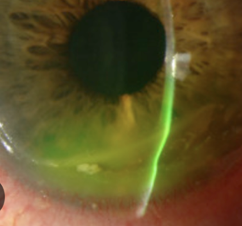

Herpes Simplex: Leading infectious cause of blindness in US and most common virus in humans (cold sores T1, or genital herpes T2). Usually dormant in trigeminal nerve but eruptions occurs, triggered by stress, sun, fever etc. 25% who get HSV keratitis will have inc likelihood of recurrence.

Signs:

skin lesions adjacent to eyes - vesicles/pustules that crust over and heal – earliest sign.

Uni follicular conjunctivitis, preauricular Lymphadenopathy.

Ulcers: Dendrites, can have geographic ulcer wider than dendrite AND marginal ulcer.

Uveitis and acute retinal necrosis

Intersitial keratitis and endotheliitis present similarly - stromal opacity

Workup: Immunoassay (Herpchek), RPS HSV detector, NAFL stain

Plan: Oral acyclovir 400mg 5 times per day with ganciclovir 0.15% 5 times for 7-10 days.

If ulcer/stroma, Acyclovir 800mg 5 times per day

If IK/endotheliitis: add Pred forte 1% QID with slow taper.

RTC 2-7 days